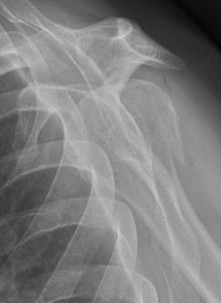

Two part

Displaced greater tuberosity fracture

Displaced lesser tuberosity fracture

Two part proximal humerus fracture

Two part proximal humerus fracture dislocation posterior